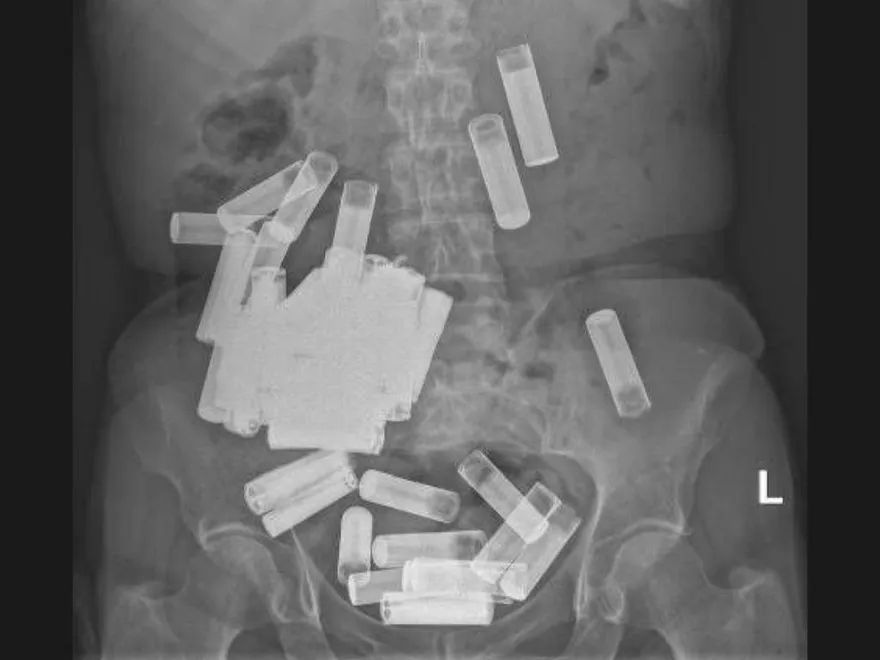

電池

X光

X光照